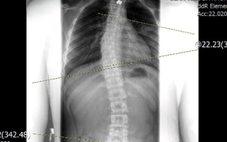

| Bệnh viện Đa khoa Quảng Nam nối thành công bàn tay bị đứt lìa của cháu Hồ Văn Nghiêm - Ảnh: T.Trần |

Khuya cùng ngày, gia đình cháu Nghiêm đã chuyển cháu đến BV Đa khoa Quảng Nam cấp cứu. Tại đây, các bác sỹ đã tiến hành phẫu phuật nối động mạch, tĩnh mạch, xương, gân… Theo các bác sĩ BV Đa khoa Quảng Nam cho biết, sau 3 ngày điều trị, đến nay bàn tay cháu Nghiêm đã hồng, ấm trở lại, sức khỏe của cháu cũng đã ổn định.